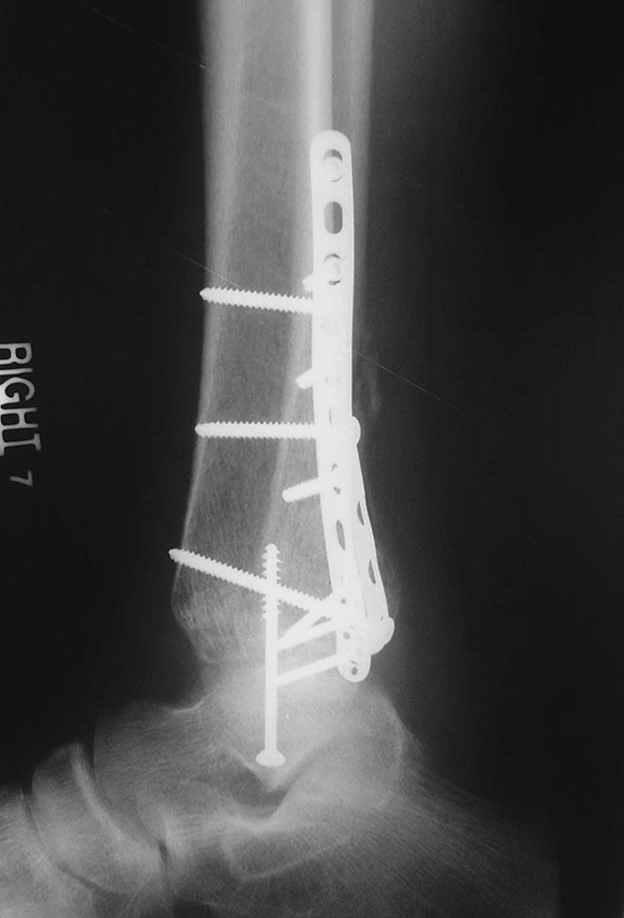

A propos fibular fixation if one is eager to stabilize it separately. In the fracture pattern a way of closed fixation by V-shaped stressed wire (advanced by colleagues from Moscow, prof. Lazarev A.F. et al.) must be excellent. We use indirect closed reduction by the external fixator. Example attached, that fibular fracture is even more suitable for plating but the wire did the job.

Еще, кстати, о фиксации лодыжки, если уж непременно хочется ее отдельно стабилизировать - при таком характере перелома замечательно должен сработать предложенный проф. Лазаревым с соратниками способ фиксации напряженной V-образной спицей. Опять же, открытая репозиция не нужна, мы делаем непрямую репозицию именно аппаратом. В приложении пример, там перелом малоберцовой куда менее поперечный, чем в данном случае, но все равно получилось закрыто без пластинки.